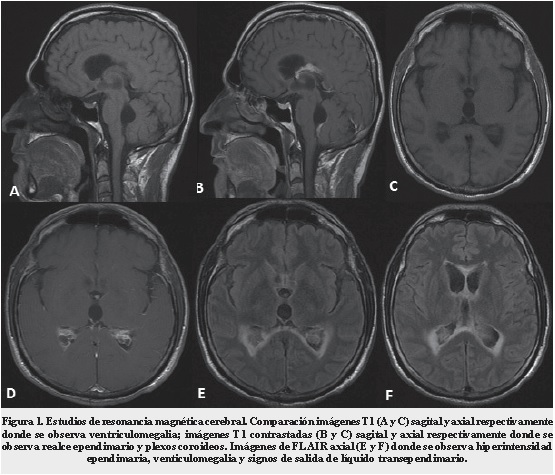

Estudios adicionales de LCR mostraron: cultivo negativo y antígeno en látex para Criptococo negativo. Dos días después se realizó Resonancia Cerebral (RM) simple y con contraste donde se observó un intenso realce subependimario en los plexos coroideos y en el área de proyección de losagujeros de Luschka. Estos cambios sugieren ventriculitis con hidrocefalia no comunicante activa (Figura 1). Debido a los hallazgos en RM se inició manejo Anti-Tuberculosis (anti-TB) y se suspendió aciclovir.